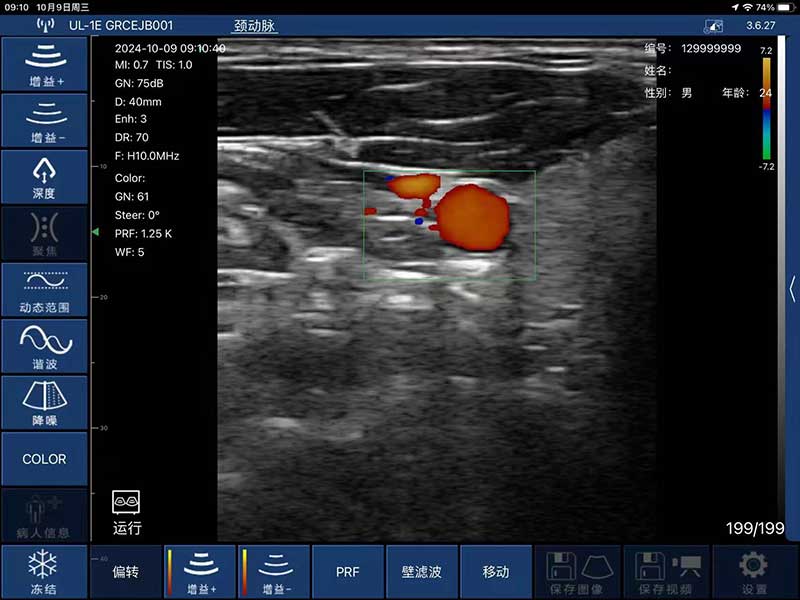

- Display mode: B, B/M, B+Color, B+PDI, B+PW

- Probe frequency: 7.5MHz/10MHz

- Scan depth: 20/40/60/80mm

- Scan width: 40mm

- Image Adjust: BGain, TGC, DYN, Focus, Depth, Harmonic, Denoise, Color Gain,

Steer, PRF

- Image frame rate: 18frames/second